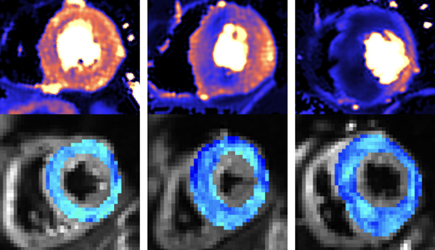

New scanning methods can detect deadly heart condition before symptoms appear

Combining two types of heart scan could help doctors to detect the deadly heart condition hypertrophic cardiomyopathy (HCM) before symptoms and signs on conventional tests appear, according to research funded by the British Heart Foundation.